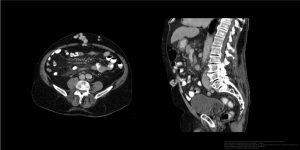

- L5 の高さで左右の総腸骨静脈が合して下大静脈となる

- 下大静脈は右側を上行するので、左腎静脈は長く、右腎静脈は短い。

- 左性腺静脈(左精巣静脈、左卵巣静脈)は左腎静脈に注ぐ

- 右性腺静脈(右精巣静脈、右卵巣静脈)は下大静脈に注ぐ